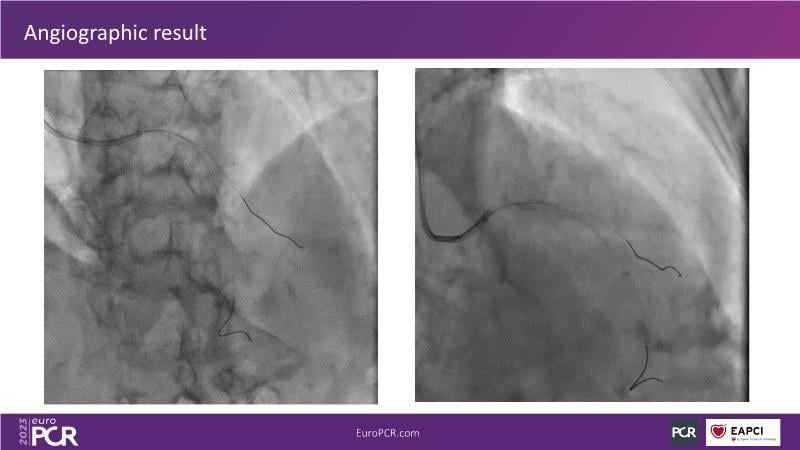

Join this session to explore the advantages of a fully optical approach in optimizing percutaneous coronary intervention (PCI) with the OptoWire III physiology wire and Nipro HF-OCT catheter. Through a practical case, you'll discover the significance of coronary physiology and intravascular imaging in bifurcation PCI and gain insights into how the performance and accuracy of the OptoWire III physiology wire can facilitate fast and reliable decision-making, particularly in side branch jailing scenarios.

- To review, through a practical case, the value of coronary physiology and intravascular imaging in bifurcation PCI